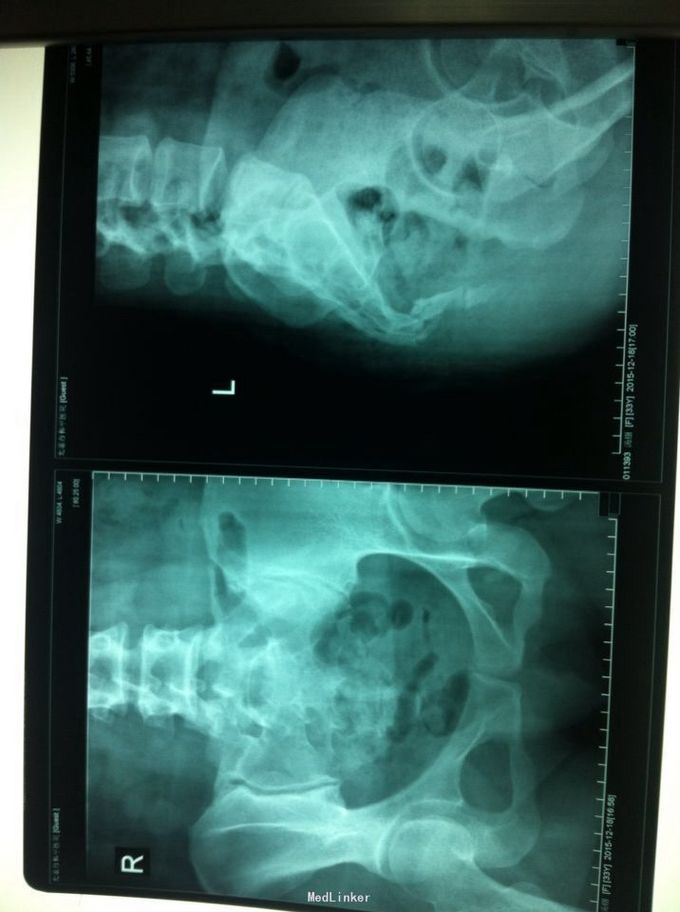

摔倒致骶尾部疼痛、行动受限2小时来院就诊,急诊拍X片示:尾椎骨骨质连续性中断伴明显移位。

查体:患者呈强迫体位,骶尾部可见局部凹陷,局部压痛明显,可及反常活动及骨擦感。 骨盆正侧位片示:尾椎骨骨质连续性中断伴明显移位。

诊断:尾椎骨骨折并移位